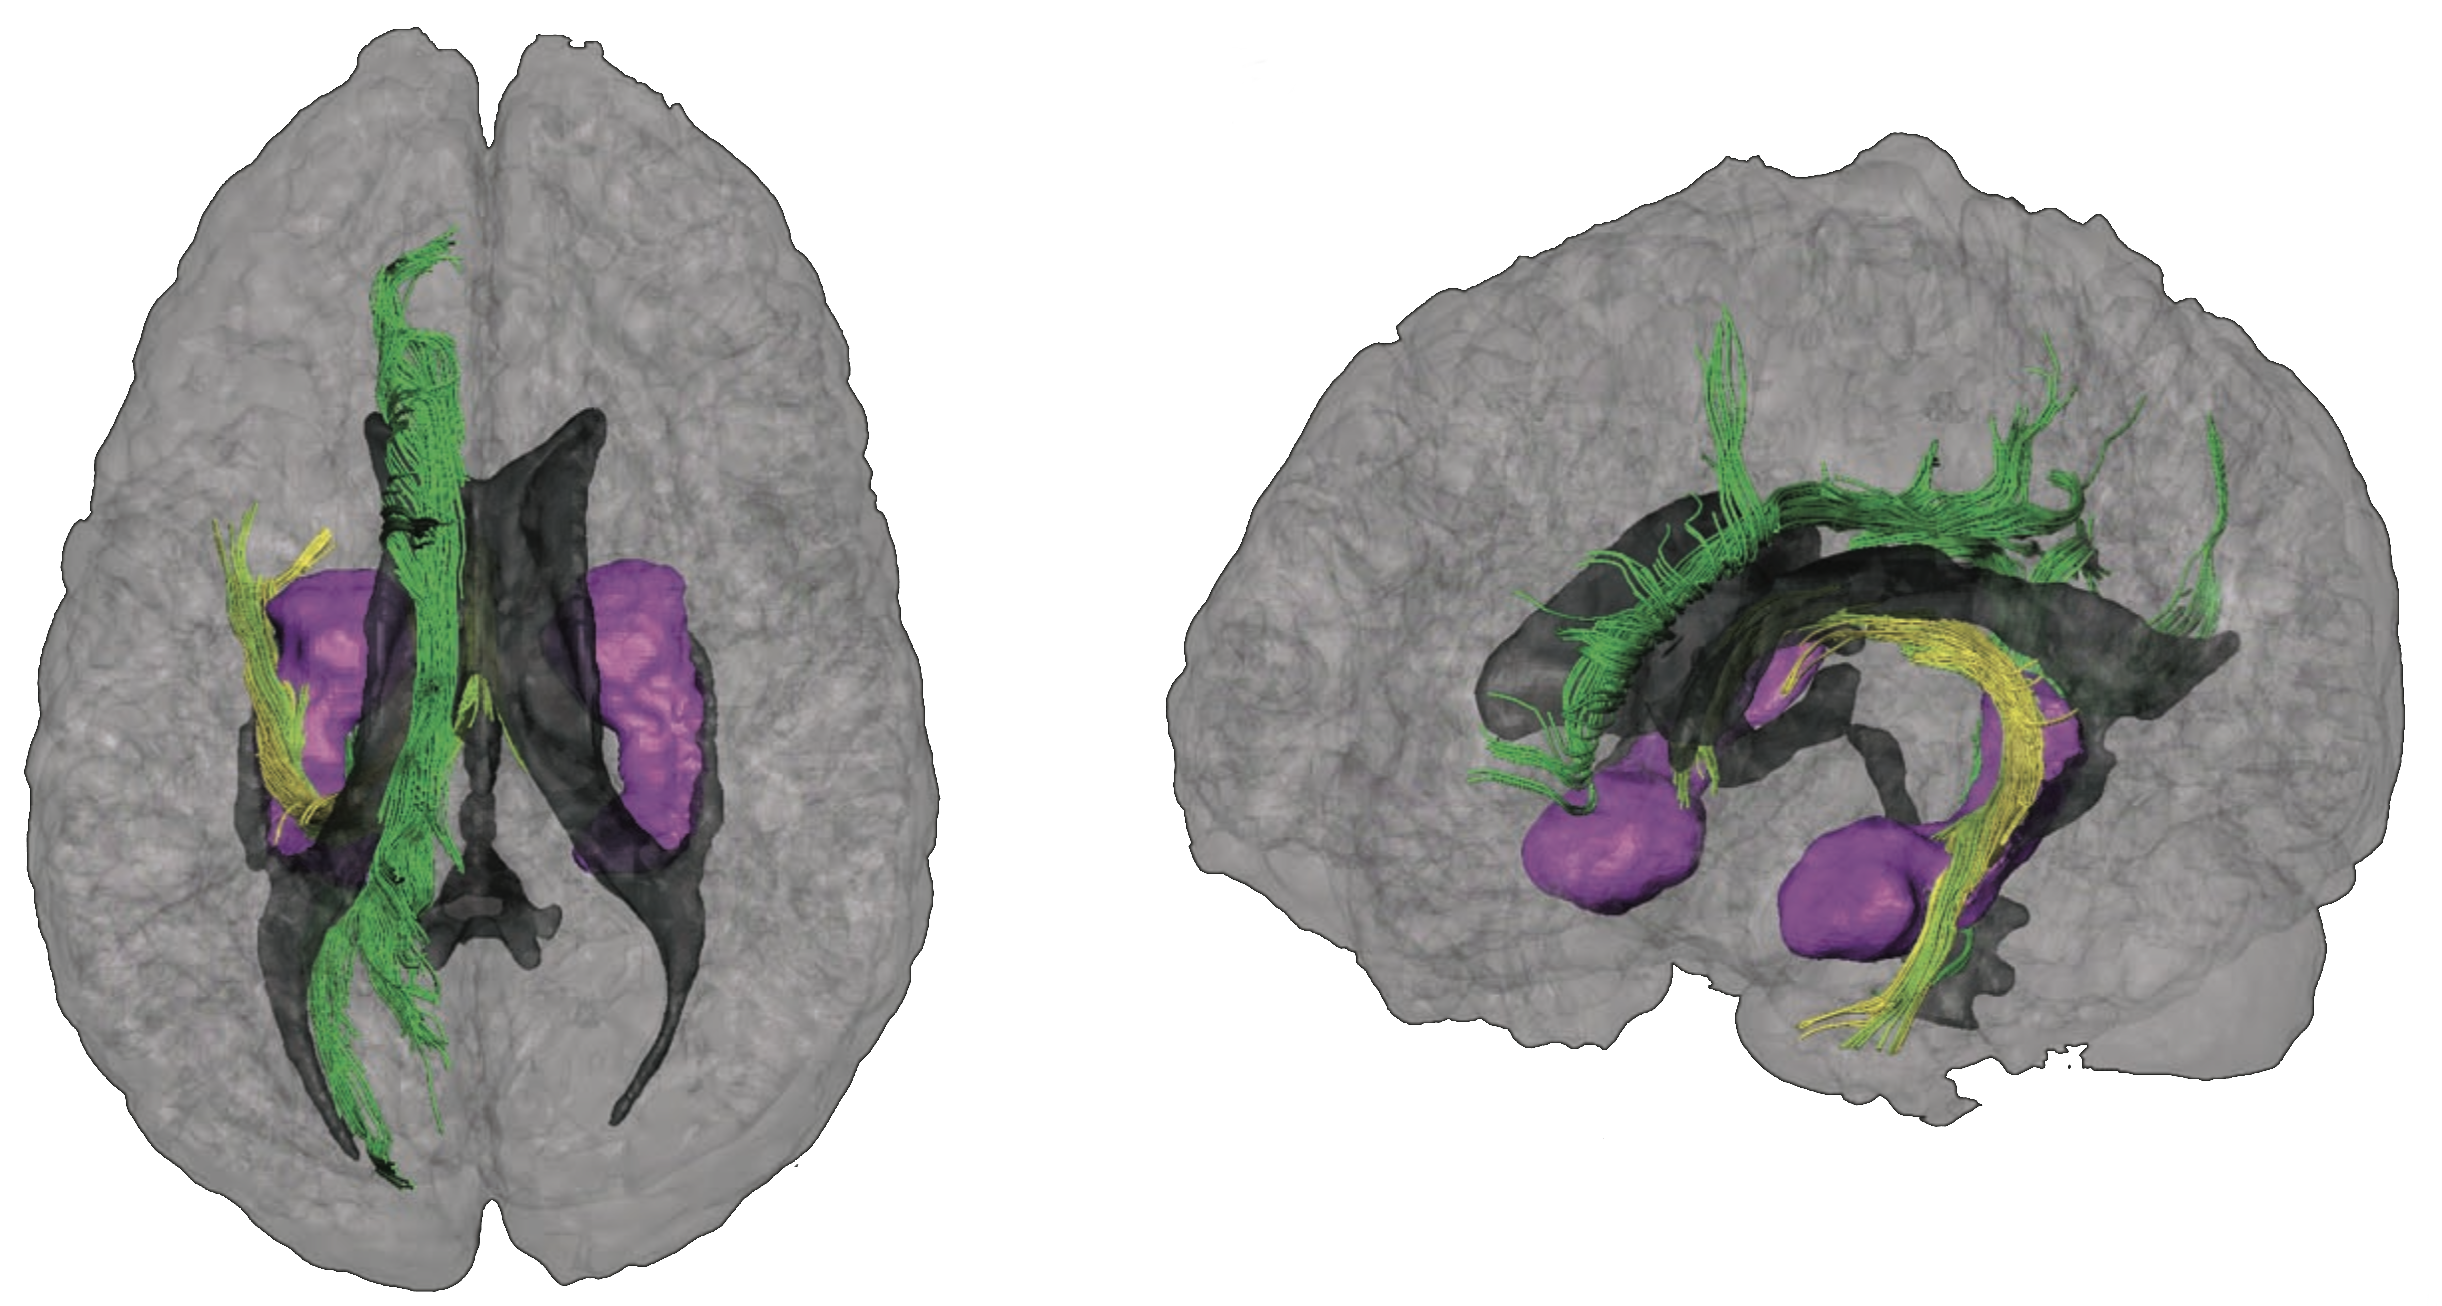

如今,外科医生在到达人体内部深层且关键的结构时,可用的方法非常有限,且现有工具仍不够精确。在神经外科领域,多种新兴疗法如深部脑刺激(Hariz等人,2013)和基因疗法(霍凯米勒等人,2016)要求对大脑深层区域进行操作,进一步凸显了这一需求。真正的医学挑战在于,在不损伤大脑重要区域的前提下,抵达深层的病理结构(图1)。事实上,从大脑皮层表面到可能位于大脑深部的目标区域之间,分布着关键的功能连接通路和供血血管,例如图2所示的白质纤维束。目前,神经外科手术依赖于高精度的成像技术,如CT(计算机断层扫描)和MRI(磁共振成像),可提供亚毫米级预规划路径(Fitzpatrick,2010;卢等人,2015)。然而,这些系统虽然具备较高的空间分辨率,却无法作为实时工具使用(时间分辨率不足),可能导致手术精度下降,因为大脑可能因脑脊液渗漏或肿瘤逐步切除而发生移位。现代术中神经影像的目标是在整个手术过程中兼顾空间分辨率和时间分辨率,同时不损失任何精度。

过去二十年微型机器人技术的进步(沙耶和斯泰凡,2013),特别是在推进和导航方面(库默等人,2010;哈利勒等人,2014;托托里等人,2011;金等人,2016;邱等人,2015;艾哈迈德等人,2016;维兰加等人,2016;戴等人,2016;索洛韦夫等人,2009;马格丹茨等人,2015),开辟了新的前景。在人体内的导航(里奇等人,2018;泰勒等人,2016;陈等人,2018),若要实现完全可控,需要一个能够在不损伤人体的情况下穿透组织和骨层提供定位测量的跟踪系统(图3)。迄今为止,关于微设备导航的研究通过在体外系统中测试并依赖基于视觉的技术来回避这一问题,而这些方法在 invivo 实验中毫无用处(乌尔马斯等人,2018;哈利勒等人,2014,2018)。由于人体组织的连续层次(图3)具有显著不同的特性,因此可能会带来大量干扰。挑战在于手术过程中实时定位亚毫米级医疗器械,同时即使在这些干扰条件下仍保持相同的精度(玛丽安娜·梅迪纳‐桑切斯和奥利弗·G·施密特,2017)。